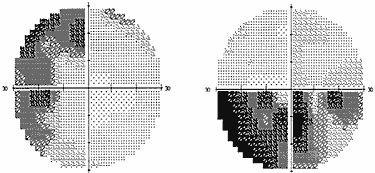

В силу различных причин, в частности, из–за строения диафрагмы турецкого седла, опухоль может распространяться не столько кверху, сколько латерально, в сторону кавернозного синуса – латероселлярный рост. Зрительные нарушения, которые присутствуют при этом росте опухоли, чаще представлены асимметричным хиазмальным синдромом со значительным, вплоть до практической слепоты, понижением остроты зрения на одном глазу. Может также развиться одноименная (односторонняя) гомонимная гемианопсия (рис. 2) в результате воздействия опухоли на зрительный тракт. Дефекты поля зрения появляются в половине поля зрения на стороне, противоположной локализации опухоли. Офтальмологи должны быть внимательны, поскольку дефекты поля зрения при латероселлярном росте опухоли и развитии асимметричного хиазмального синдрома или гомонимной трактусной гемианопсии появляются в носовой половине поля зрения на глазу на стороне преимущественного роста опухоли (рис. 3). Это может спровоцировать ошибочную диагностику глаукомы.

Рис. 2. Полная правосторонняя гомонимная гемианопсия (автоматическая статическая периметрия)

Рис. 3. Начальная левосторонняя гомонимная гемианопсия (автоматическая статическая периметрия)